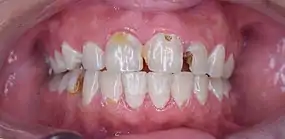

La carie dentaire, ou simplement carie, est une maladie infectieuse de la dent, qui se manifeste par une lésion de l'émail, du cément ou de la dentine, voire de la pulpe. Elle est très souvent noire et forme un creux dans la dent.

- Dommages visibles : initialement tache blanche (pas toujours très visible). Une tache marron (plus ou moins foncée) signale une carie ancienne, reminéralisée, qui n'est plus active.

Lorsqu'on remarque un trou dans la dent, la carie est déjà avancée ; la dent risque de devoir être dévitalisée.